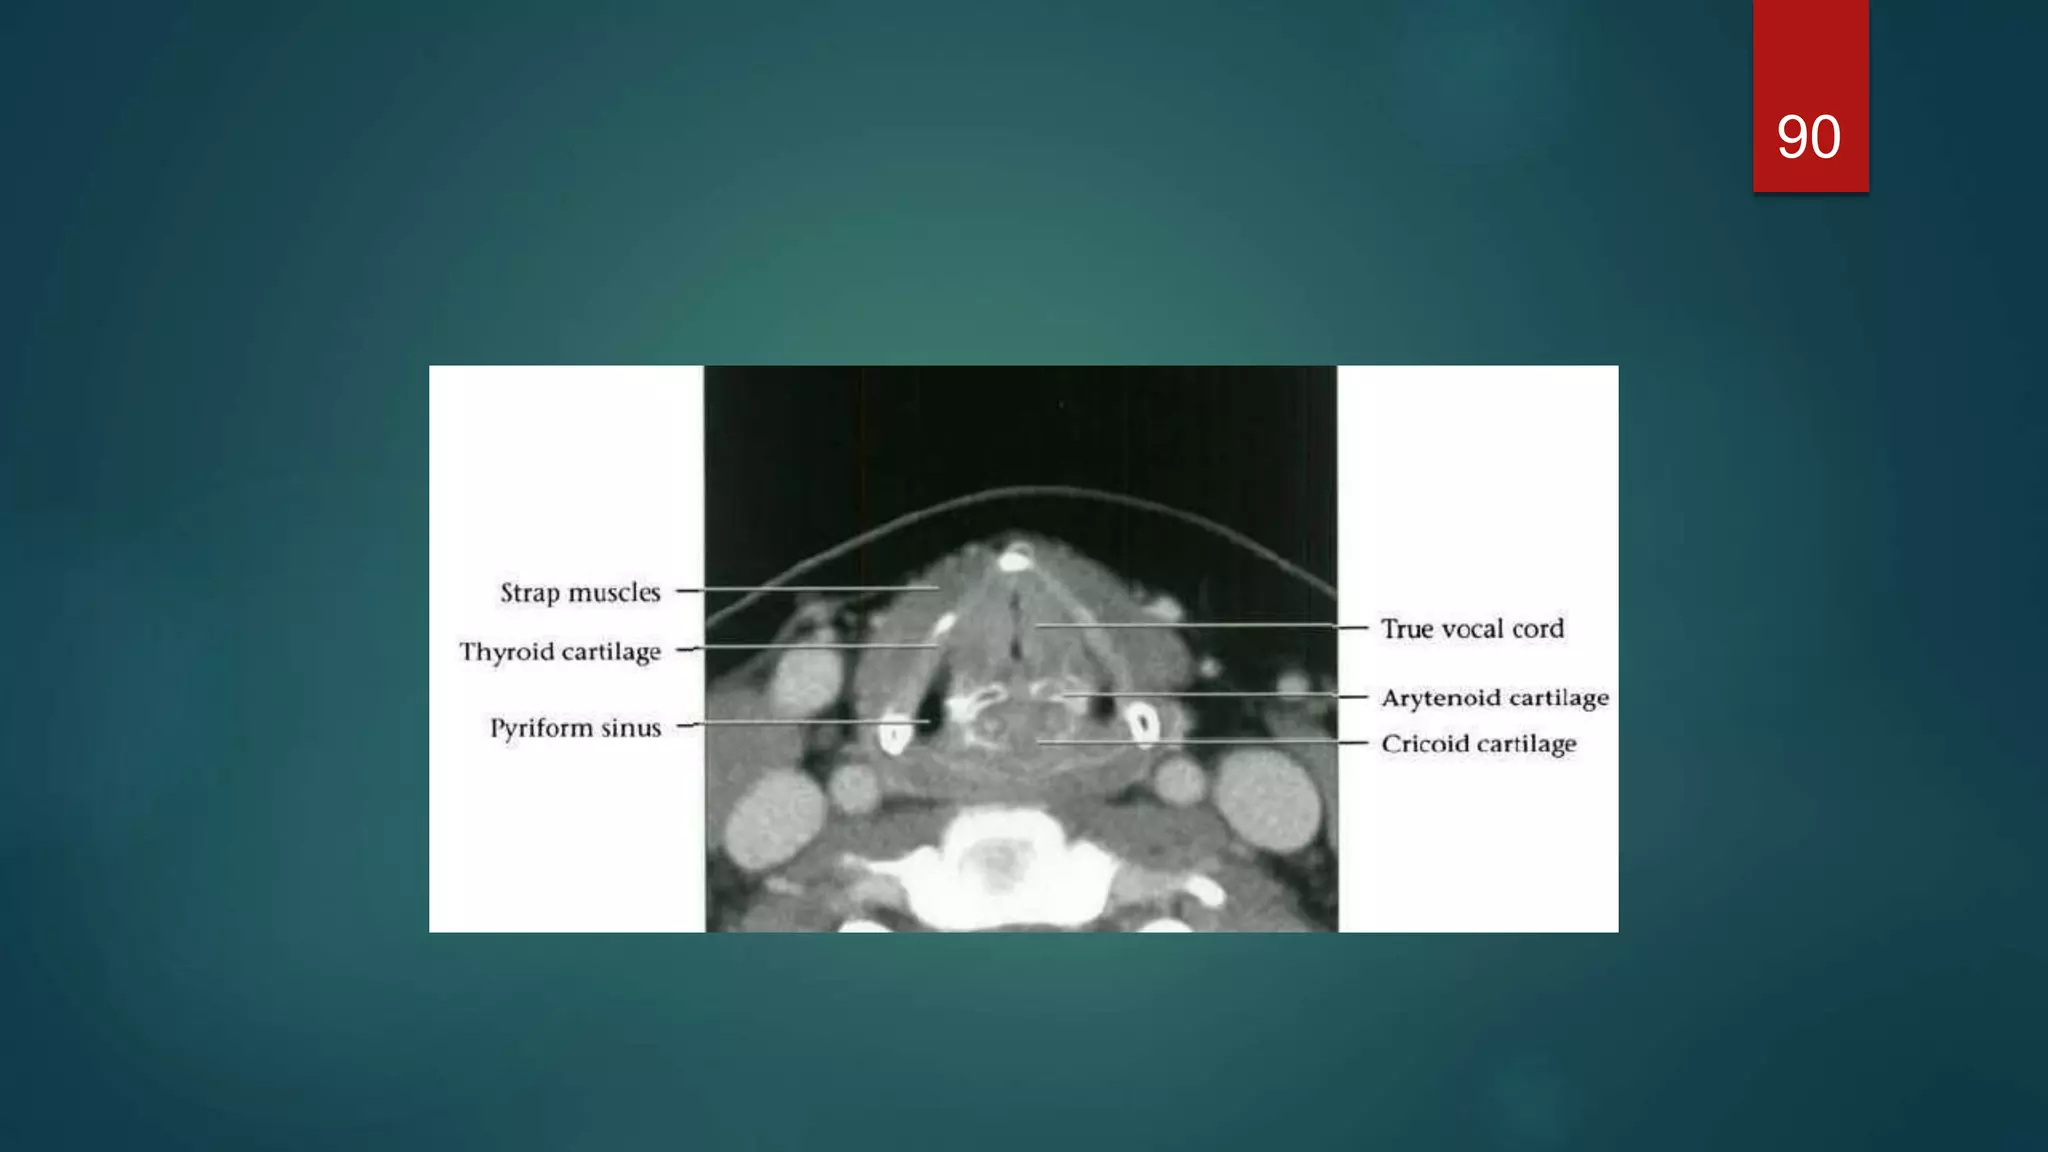

Glottic level

 A complete ring of cartilage is seen at this level –thyroid cartilage anteriorly

& lamina of the cricoid &arytenoid cartilages posteriorly.

 The anterior fusion of the vocal cords is known as the anterior commissure

and is very thin when the cords are abducted. Similarly, the posterior

commissure, which is seen between the arytenoids

 The larynx is elliptical in shape at the level of the true cords and triangular at

the level of the false cords, which are at a slightly higher level.

Glottic level  Acomplete ring of cartilage is seen at this level –thyroid cartilage anteriorly & lamina of the cricoid &arytenoid cartilages posteriorly.  The anterior fusion of the vocal cords is known as the anterior commissure and is very thin when the cords are abducted. Similarly, the posterior commissure, which is seen between the arytenoids  The larynx is elliptical in shape at the level of the true cords and triangular at the level of the false cords, which are at a slightly higher level. 74